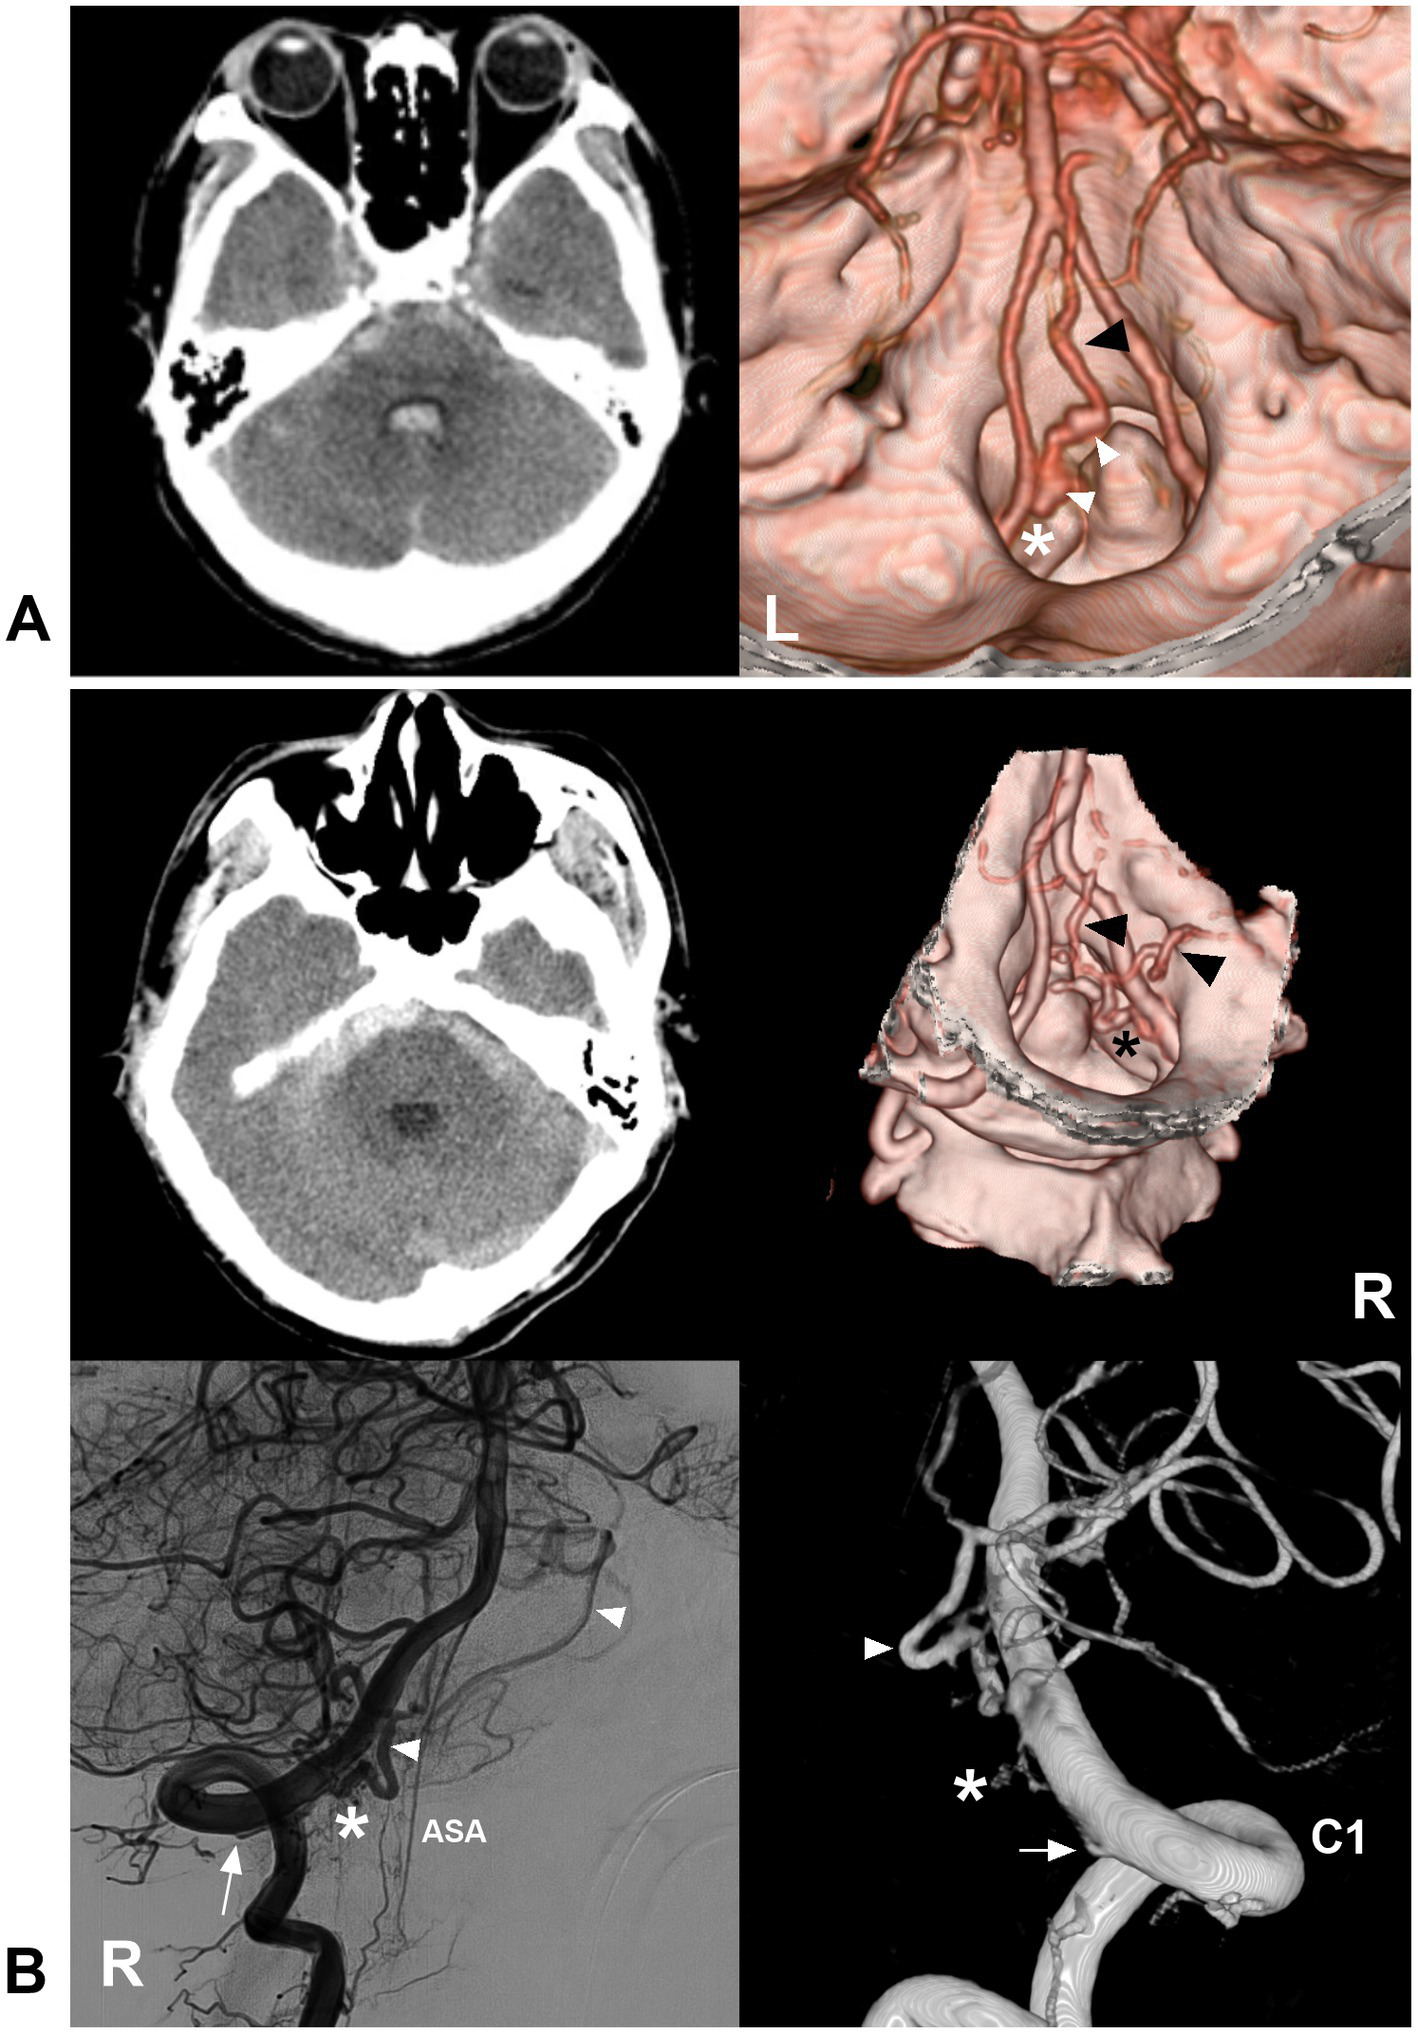

Figure 9

Ruptured CCJ AVF with upward drainage. (A) Left panel: CT showing subarachnoid hemorrhage and fourth ventricle hemorrhage; Right panel: CTA showing that a CCJ AVF (asterisk) had upward venous drainage (black arrowhead) with varices (white arrowheads). (B) Left upper panel: CT showing subarachnoid hemorrhage; right upper panel: CTA showing that a CCJ AVF (asterisk) had upward venous drainage (arrowheads); two-dimensional DSA (left below panel) and three-dimensional DSA (right below panel) showing a RAVF (asterisks) fed by the C1 radicular artery (arrows). The drainage went into the intracranial vein (arrowheads). AVF, arteriovenous fistula; C1, first cervical vertebrae; CCJ, craniocervical junction; CT, computed tomography; CTA, CT angiography; DSA, digital subtracted angiography; RAVF, radicular AVF.